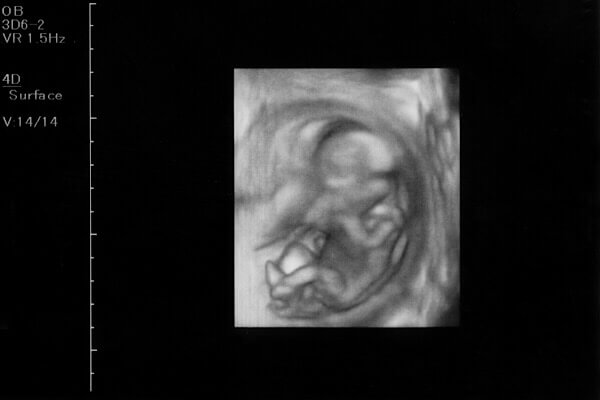

妊娠13週目の赤ちゃんの様子

赤ちゃんの大きさ

妊娠13週目の赤ちゃんの頭殿長(CRL)は約75mm、体重は30〜40g程度です。

これまでの妊婦健診ではエコー検査で赤ちゃんの発育具合を確認するのは赤ちゃんの頭からお尻までの長さである頭殿長(CRL)でしたが、13週ごろからは赤ちゃん頭の横幅、児童大横径(BPD)を計測するようになります。

器官の形成が終わり、手足の骨や筋肉が発達

心臓、肝臓、胃、腸などの内臓器官の形成が終わり、これから体や手足の骨、筋肉などが発達していきます。羊水の量が増え、その中で手や足を動かすようになります。

赤ちゃんの皮膚はまだ透明ですが、厚みを増してさらに産毛が生えてきます。目は閉じていますが、口は開けたり閉じたりしています。

胎盤が完成するのは15週頃。エコーで胎盤からへその緒が出ていることも確認できるようになってきます。